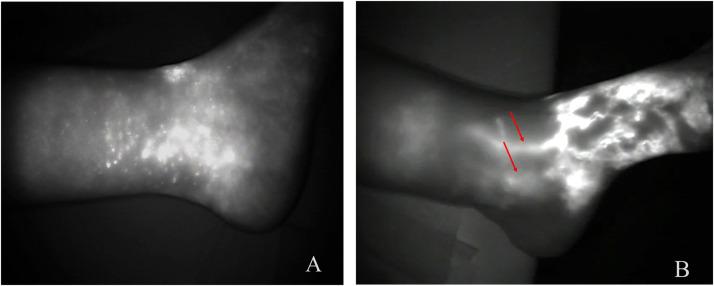

Mean follow-up was period was 42 months (24-60 months) in Group-A, and 27 months (18-48 months) in Group-B patients. Demographic data, lymphedema etiology, and staging were comparable in both groups. Pre- and post-operative edema volume difference for Group-A was 36 % and 25 % ( < 0.001), and 33 % and 14 % in Group-B ( = 0.001), respectively. The mean number of infection episodes decreased in Group-A and B from 1.75 to 0.33 and from 2.17 to 0.42 per patient/year, respectively. ICG mean stage in Group-A was 3.58 pre- and 3 post-operatively ( = 0.045), and 3.67 pre- and 2.08 post-operatively in Group-B ( = 0.506). A statistically significant difference was found in post-operative volume difference between the 2 groups ( = 0.008) and post-operative ICG changes ( < 0.001). ICG-lymphography demonstrated new lymphatic vessel formation at the NCS implantation location.

A组患者的平均随访期为42个月(24 - 60个月),B组患者为27个月(18 - 48个月)。两组的人口统计学数据、淋巴水肿病因和分期具有可比性。A组术前和术后水肿容积差异分别为36%和25%(P < 0.001),B组分别为33%和14%(P = 0.001)。A组和B组患者每年的平均感染发作次数分别从1.75次降至0.33次和从2.17次降至0.42次。A组ICG平均分期术前为3.58,术后为3(P = 可见 0.045),B组术前为3.67,术后为2.08(P = 0.506)。两组术后容积差异(P = 0.008)和术后ICG变化(P < 0.001)存在统计学显著差异。ICG淋巴管造影显示在NCS植入部位有新的淋巴管形成。